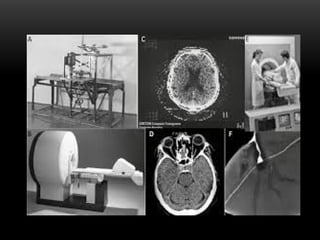

HISTÓRIA DA TOMOGRAFIA

Ela foi inventada pelo engenheiro eletrônico

britânico Sir Godfrey Newbold Hounsfield, em

1972, e descrita no Congresso Britânico do

Instituto de Radiologia. Por isso, o nome Escala

Hounsfield: que é uma escala utilizada em

tomografia computadorizada para distinção dos

tons de cinza ao avaliar cada estrutura anatômica

(falaremos disso adiante).

PRIMEIRA GERAÇÃO

• Surgiu em 1972. Era um procedimento

extremamente demorado, visto que exigia

aproximados 5 minutos para reunir informações

suficientes de cada corte. Ou seja, após a primeira

varredura, o tubo sofria uma rotação de grau para

iniciar uma nova varredura. Assim, sucessivamente

por 180 vezes.

Ela foi inventadapelo engenheiro eletrônico britânico Sir Godfrey Newbold Hounsfield, em 1972, e descrita no Congresso Britânico do Instituto de Radiologia. Por isso, o nome Escala Hounsfield: que é uma escala utilizada em tomografia computadorizada para distinção dos tons de cinza ao avaliar cada estrutura anatômica (falaremos disso adiante).

A primeira utilizaçãooperacional de um tomógrafo computadorizado no mundo foi em Atkinson Morley Hospital, em Londres, berço dos estudos de Hounsfield. Além disso, o primeiro equipamento de TC, só permitia a avaliação do metabolismo cerebral ou de tumores do cérebro.

PRIMEIRA GERAÇÃO • Surgiuem 1972. Era um procedimento extremamente demorado, visto que exigia aproximados 5 minutos para reunir informações suficientes de cada corte. Ou seja, após a primeira varredura, o tubo sofria uma rotação de grau para iniciar uma nova varredura. Assim, sucessivamente por 180 vezes.